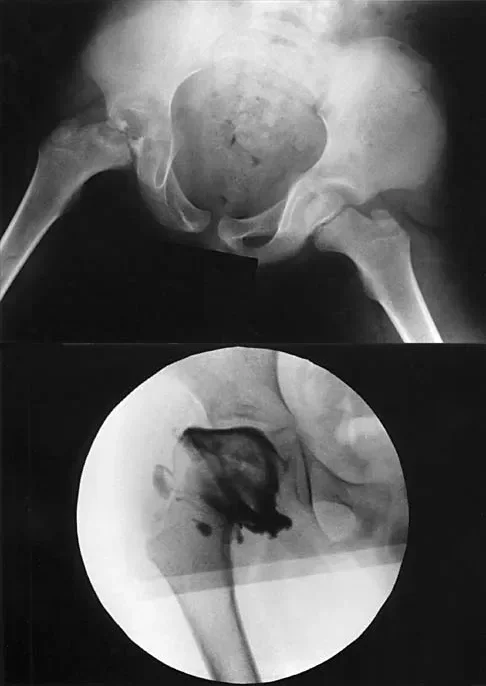

A 7-year-old boy with Legg-Calvé-Perthes disease presents with a painful limp and limited abduction. Radiographs demonstrate hinge abduction. What is the primary pathomechanical consequence of persistent hinge abduction if left untreated?

Explanation

Correct Answer: B

Hinge abduction occurs when the extruded, enlarged anterolateral portion of the femoral head impinges on the lateral margin of the acetabulum during abduction. Persistent hinge abduction prevents the acetabulum from effectively remodeling the femoral head, leading to a permanently deformed, aspherical femoral head (coxa magna) and early osteoarthritis. It does not cause premature closure of the triradiate cartilage or avascular necrosis of the acetabulum.

A 7-year-old boy with a history of a painless limp is diagnosed with Legg-Calvé-Perthes disease. An arthrogram is performed to evaluate joint congruency. The maximum abduction/internal rotation view is shown in Figure A, and the abduction view is shown in Figure B. The failure of the lateral epiphysis to slide under the acetabular edge with abduction, accompanied by medial dye pooling, is pathognomonic for which of the following conditions?

Correct Answer: Hinge abduction

The arthrogram images demonstrate classic hinge abduction, a critical finding in severe Legg-Calvé-Perthes disease. Hinge abduction occurs when the enlarged, deformed lateral portion of the femoral head extrudes and impinges against the lateral margin of the acetabulum during abduction. Instead of gliding smoothly into the acetabulum, the femoral head hinges on the acetabular rim, causing the medial joint space to widen (distract), which is visualized as medial dye pooling on the arthrogram. Persistent hinge abduction prevents normal spherical remodeling of the femoral head and is an indication for surgical intervention to restore congruency.

A 7-year-old boy with a history of a painless limp undergoes an arthrogram of the hip, as shown in the provided images. The failure of the lateral epiphysis to slide under the acetabular edge during abduction is diagnostic of which of the following?

The arthrogram demonstrates hinge abduction, a severe complication of Legg-Calvé-Perthes disease where the deformed, extruded lateral portion of the femoral head hinges against the lateral acetabular margin during abduction, preventing concentric reduction. This persistent hinge abduction prevents femoral head remodeling by the acetabulum.

A 7-year-old boy with a history of a painless limp presents with limited abduction and spasm on internal rotation. Radiographs obtained during an arthrogram are shown. The failure of the lateral epiphysis to slide under the acetabular edge during abduction is diagnostic of which of the following?

The radiographs demonstrate classic hinge abduction in a patient with Legg-Calve-Perthes disease. Hinge abduction occurs when the enlarged, deformed lateral portion of the femoral head impinges on the lateral acetabular margin during abduction, preventing the head from sliding concentrically into the acetabulum. The arthrogram shows medial dye pooling due to distraction of the joint. Persistent hinge abduction prevents proper femoral head remodeling and is an indication for surgical intervention.